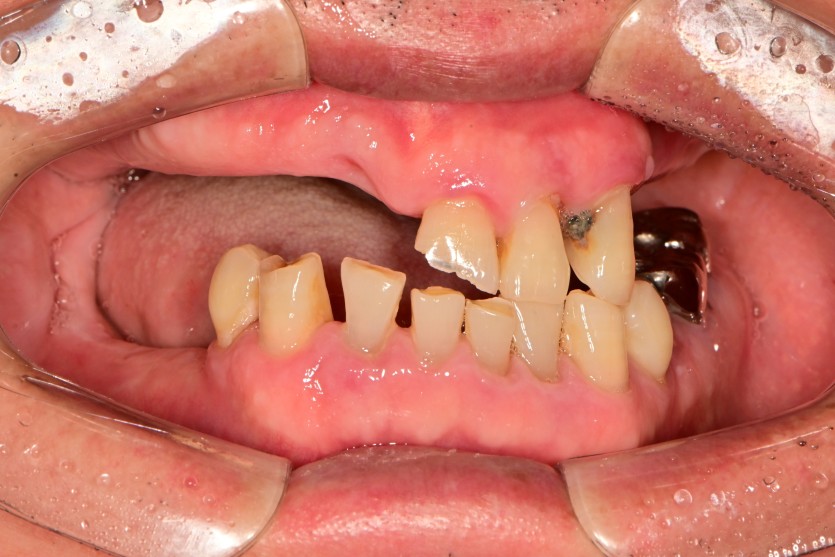

전체 임플란트 증례입니다.

15개의 임플란트로 완성하였습니다.